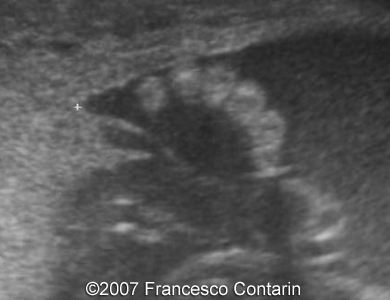

Images 3, 4. 29th week of pregnancy -  shortened tibia (left); and polydactyly of the hand (right).

3

4